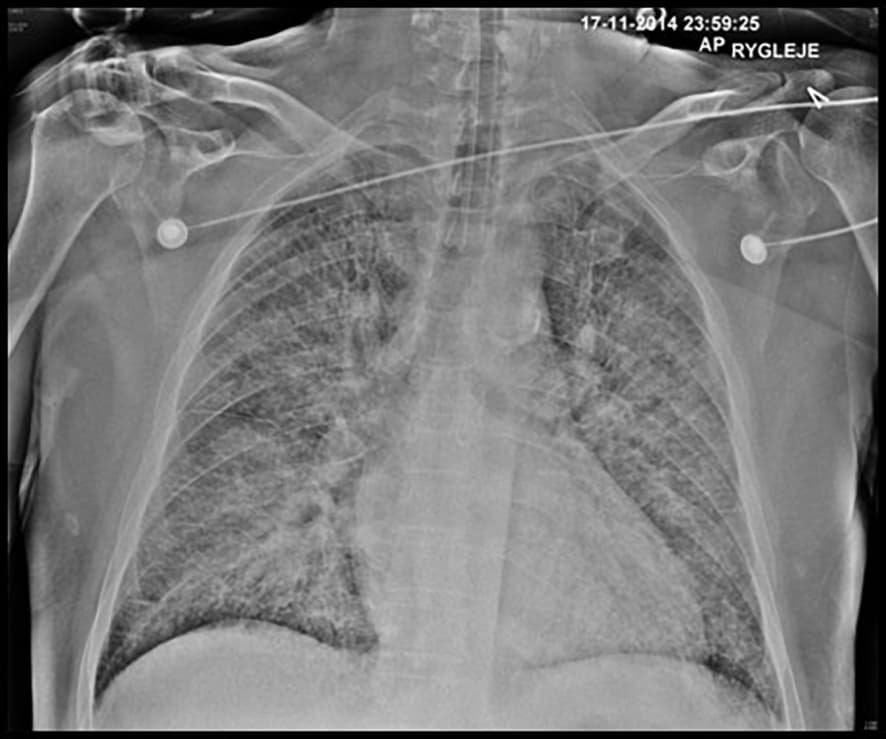

Eksempel på lungeødem. Røntgenbilledet af thorax er taget anterior-posteriort med patienten i rygleje, hvilket næsten altid er tilfældet, da patienter med akut hjertesvigt sjældent kan medvirke til stående optagelser.

Symptomer er akut indsættende dyspnø og angst/ubehag. Ved klinisk undersøgelse findes der stetoskopisk lungekrepitation og tredje hjertelyd, takykardi og ofte ingen eller mindre perifere ødemer. Røntgenoptagelser af thorax viser lungestase eller regelret lungeødem med diffuse, vattede infiltrater. Ekkokardiografi viser typisk bevaret eller nærnormal systolisk ventrikelfunktion samt eventuelt diastolisk dysfunktion og tegn til forhøjede fyldningstryk. Patienterne vil have bevaret perfusion (varm og våd).